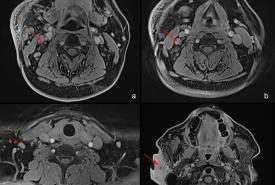

Recurrent Kimura Disease of the Submandibular Region After Prolonged Remission to Radiotherapy and Its Challenges